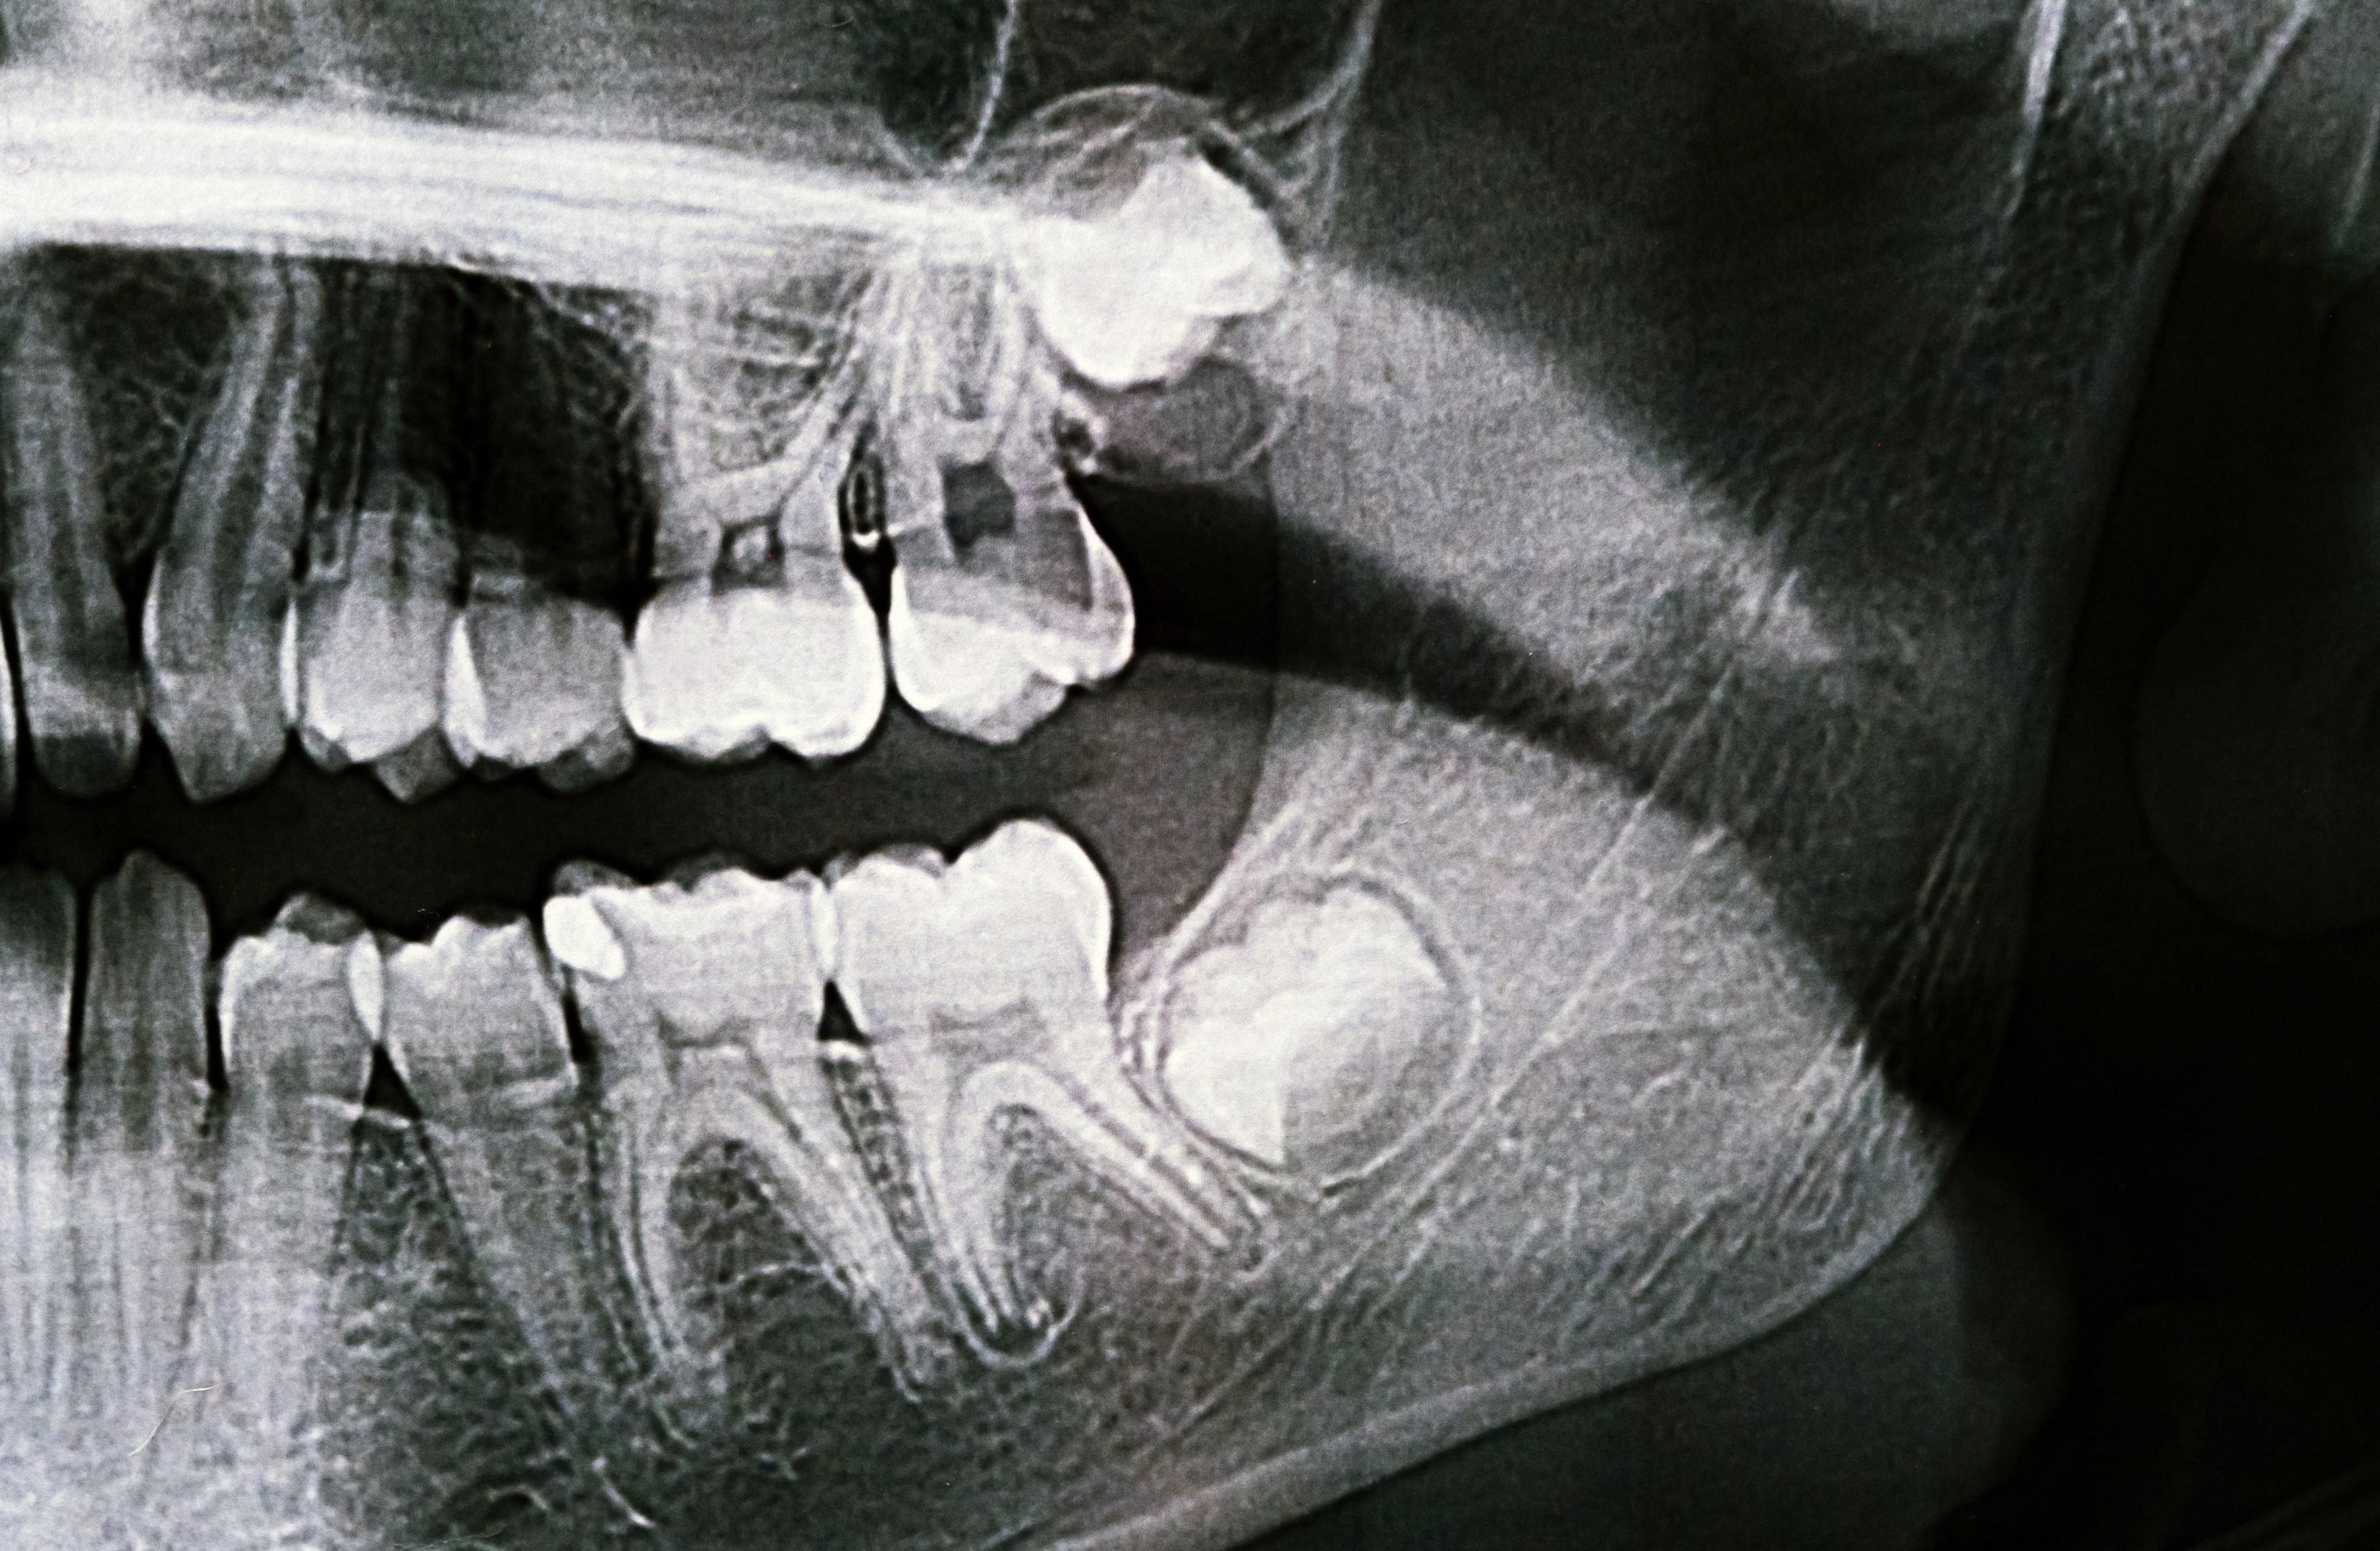

Practical Tip: Schedule regular dental X-rays for your child starting around age 14 to monitor the growth of wisdom teeth. Early detection of issues can make the removal process smoother.

Pre-surgical planning is crucial for a successful wisdom tooth extraction. Your dentist will conduct a thorough examination and take X-rays to determine the position of your wisdom teeth and the complexity of the extraction.

Before the wisdom tooth removal, your child will need a thorough consultation with the oral surgeon. This visit typically includes a discussion about the procedure, a review of your child’s medical history, and X-rays or 3D imaging to assess the position of the wisdom teeth.